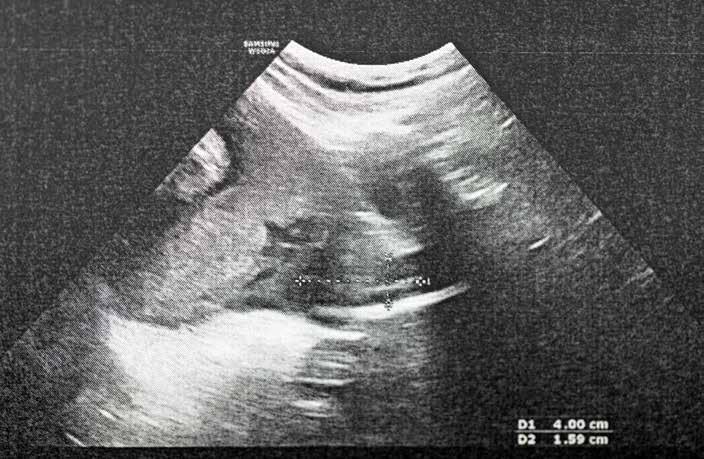

Mange forbinder ultralyd med undersøkelse av fosteret i den gravides mage, men ultralyd brukes også for å se hvordan hjertet, leveren, lungene, milten, nyrene og livmoren fungerer. Særlig i akuttmedisinen er ultralyd blitt et svært viktig verktøy. Hvert år rammes 3000 mennesker i Norge av plutselig hjertestans, og da er ultralyd et livsviktig redskap for å identifisere årsaken til hjertestansen og finne rett behandling. Er det blod i hjerteposen? Trekker hjertet seg sammen?

Ultralyd brukes også for å lokalisere blodårer og vite hvor man skal legge inn kanyler, og for å se om det er blødninger i buken eller i brysthulen.

ULTRALYD I HELIKOPTERET

På sykehusene utføres ultralydundersøkelsene ved hjelp av store datamaskiner og skjermer med utmerket bildekvalitet. Men når luftambulansen rykker ut, har legen med seg et lite, håndholdt ultralydapparat på størrelse med en stor mobiltelefon. Stiftelsen Norsk Luftambulanse har stått bak forskningen som har bidratt til å spare pasienter for smerte og risiko. De siste ti årene har de bærbare ultralydapparatene blitt svært presise, og de er nå i daglig bruk i legehelikopteret. Det gjør at legene kan gjøre mer presise vurderinger av pasientens tilstand – som å bekrefte eller avkrefte et medisinsk problem, og gi livsviktig veiledning om hva som er riktig behandling videre.